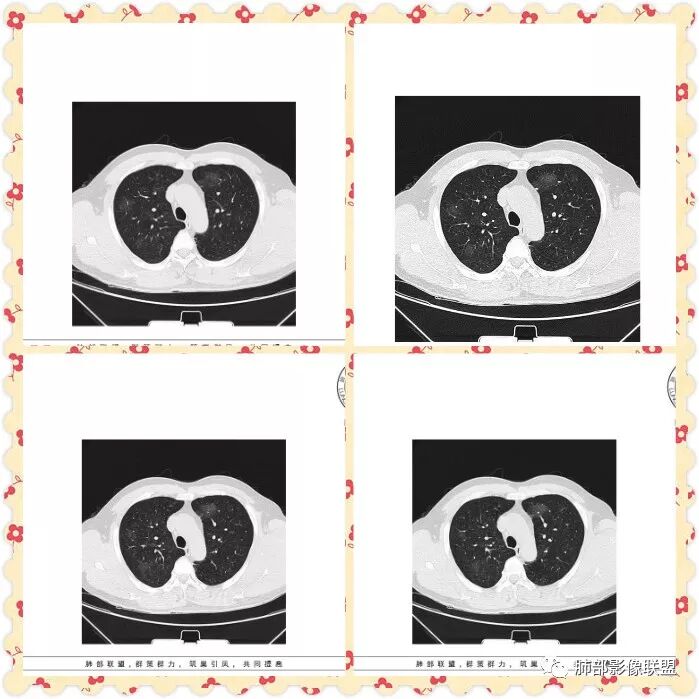

双肺多发磨玻璃影,大部分中央可见增粗血管影,部分血管边缘模糊破坏,左侧肩胛骨骨质破坏,周围巨大软组织肿块,软组织肿块内可见坏死及肿瘤骨,考虑肩胛骨骨肉瘤并双肺多发转移(点晕征)。

管洪林:

47岁男性,咳血痰左肩背痛1月余,左肩胛骨破坏,破坏处及周边见软组织肿块,左肩胛区包块并皮肤破损,破损处无渗液、无脓不支持结核。两肺见多发磨玻璃影,沿血管走行,其内血管明显增粗,部分磨玻璃影内可见点状实性结节,呈点晕征,各磨玻璃影形态密度基本一致,提示同一来源,支气管未见明显增厚扩张——不支持气道来源。小叶间隔无增厚及纵隔未见明显肿大淋巴结——感觉淋巴瘤可能性较小。胸腹部皮肤散在红斑。整体考虑左肩胛骨恶性肿瘤并两肺转移。

影像特征:左肩胛骨区巨大软组织肿块,可见肩胛骨骨质吸收破坏,肺内多发随机分布结节,和血管关系密切,周围模糊GGO影,结合病史,左肩肿块考虑原发肿瘤,肺内考虑血行性转移伴出血;

1.双肺多发磨玻璃结节影,边界可分辨,病灶中央都可见一实性密度小结节影,注意不是钙化。这些病灶形态及密度是如此相似,宛如身着厚厚一层晕影蜉蝣深海之中,称之为“点晕征”。

注意:多发、点、厚晕

2.肺部“点晕征”病灶更多见于血管肉瘤、上皮样血管内皮细胞瘤、肺动脉肉瘤等等。